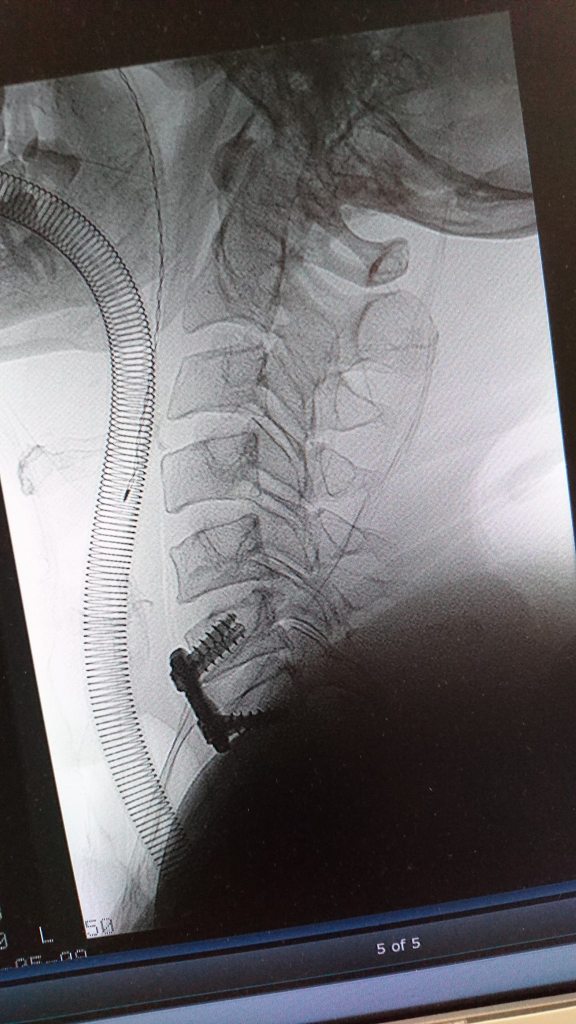

Previous Image Next Image 33532263_10155797164272408_8923004748844498944_o The screws that were loose in Vicki